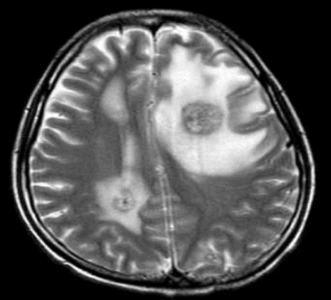

脳MRI(図1)

たとえ「がんの脳転移」と診断を付けられても慌てる必要はございません。転移性脳腫瘍は脳組織を壊すというよりも、大きくなって周りの正常脳を圧迫しながら成長することが特徴です。ですので、小さなものや未症状のものに関しては急に状態を悪くさせることはまずございません。その個数・大きさ・局在(場所)・脳への影響(脳浮腫など)・全身状態を総合的に考えて、しかるべき時期にしっかりと脳治療を行うべきとわれわれは考えています。いまは、脳転移で命を落とす時代ではありません。だからこそ、しっかりと主治医の意見に怖がらずに耳を傾けてください。